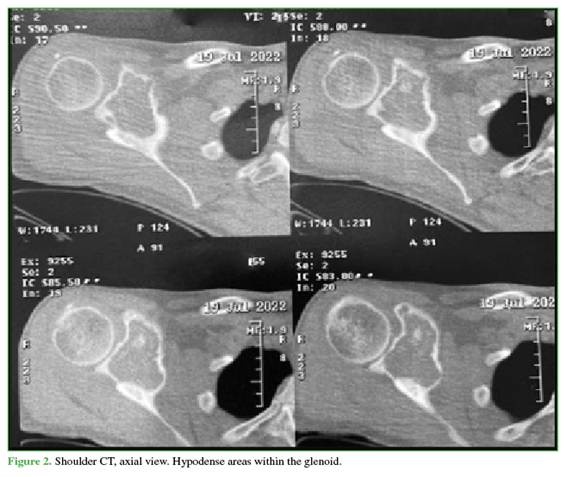

A 47-year-old man presented with right shoulder pain of one year’s duration. Physical examination revealed pain and functional limitation with restriction of all ranges of shoulder motion. Shoulder radiographs, computed tomography (CT), and magnetic resonance imaging (MRI) were obtained. Imaging showed a lobulated, expansile lesion with cortical ballooning and internal calcifications (Figure 1). On sagittal CT slices, hypodense areas were visible within the glenoid, and on T2-weighted MRI there was hyperintensity in the supraspinous fossa involving the infraspinatus and subscapularis muscles (Figure 2).